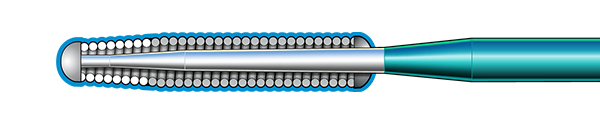

Inner Coil Technology

The advanced design of the stainless steel core and Inner Coil Technology provides a unique combination of exceptional torqueability, rail support, and shape retention.

- Stainless steel inner coil affixed directly to the distal end of the guidewire core

- Improved durability and ease of shaping

- Exceptional torqueability without whipping

Micro EMTTM Technology

MICRO EMT exactly matches the taper of the core and coil, allowing for a lower profile and a more flexible core, leaving almost no room for the core to move within the coil, resulting in 1:1 torque.

- Entry: The smallest tip on the market (0.008”) and the long taper (6 cm) facilitate easy lesion entry in even the most complex lesions.

- Maneuverability: A flexible distal shaft enables excellent intraluminal navigation in complex lesions, with minimal perforation risk.

- Torque: With exactly matched tapers, the core and coil move as one, eliminating whip and empowering precise steerability.